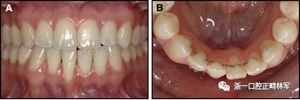

圖3.極軟弓絲完全完好,在多個空間平面上的拱形歪斜,右側尖牙的面部傾斜以及右側側切牙和中切牙在相反方向上的扭矩:A,頰面視圖; B,咬合面視圖。

圖4柔軟的螺旋弓絲保持器,下頜右側尖牙嚴重的舌側傾斜以及下頜左側尖牙的唇側移位:A,正面視圖; B,咬合面視圖(John Iaculli博士提供)。